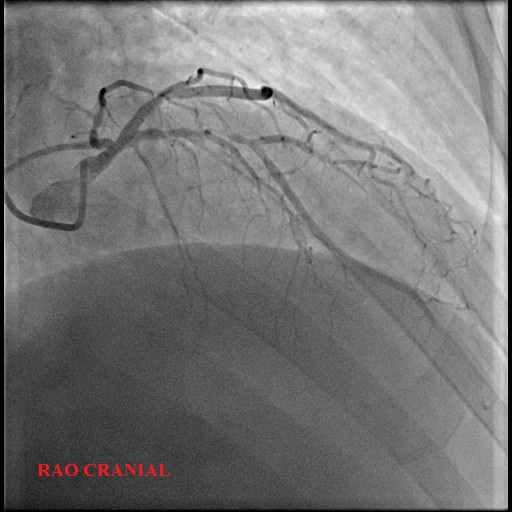

Left Main: moderate distal stenosis 40%

LAD: severe stenosis proximal 95%, TIMI 3

LCx: Small, non-dominant, diffuse disease

RCA: mild proximal disease 20%